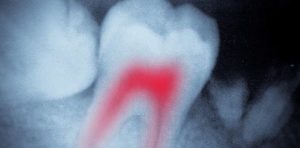

Root Canal Xray

Endodontics is the area of dentistry that relates to the pulp tissue located within the inside of teeth. This pulp can become infected for different reasons, such as a fracture or advanced tooth decay.

At Anna House, we can save and restore the affected tooth with root canal treatment. Our dental team can expertly clear away the damaged tissue and replace it with a special substitute called gutta-percha to save and strengthen the tooth – and avoid the need for it to be extracted.